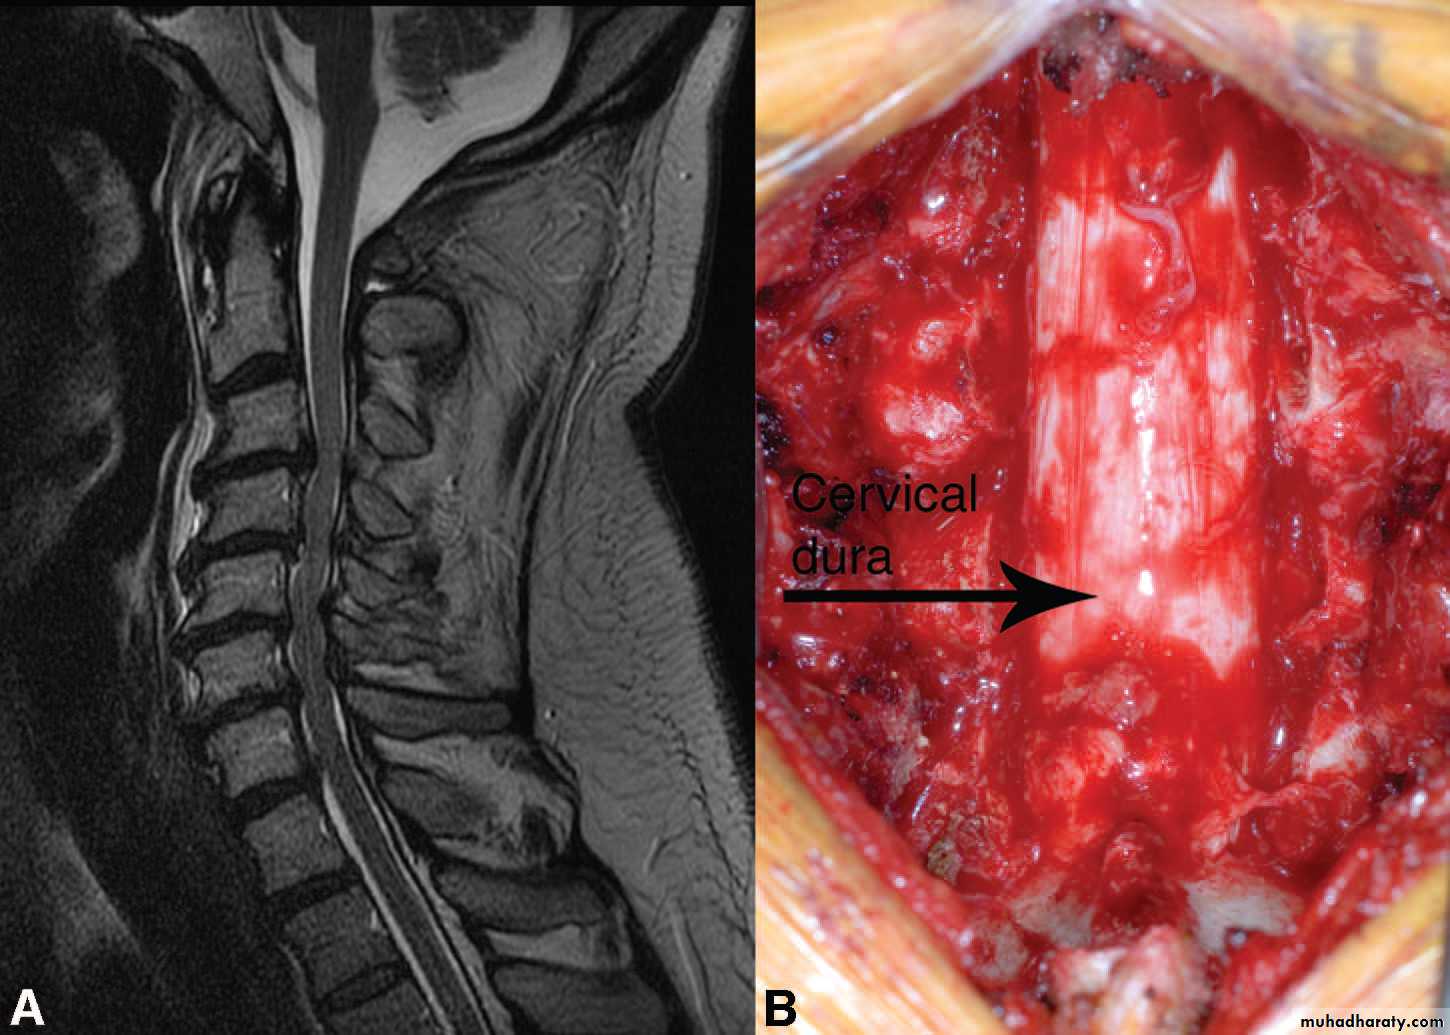

Cervical disc herniation

The clinical presentation:1-patient is usually young age develop pain in the cervical area that may radiate to the arm .

2-if the herniation is lateral so lead to radicular symptoms.

3- But if the herniatin is central so lead to compression on the spinal cord itself causing spastic quadriplegia with sensory level and incontinence.

The investigation:

1- MRI of spine :to see the direction and extent of the compression .Treatment :

Syringomyelia:

Syringomyelia is a cystic dilation or fluid-filled cavity within the spinal cord that typically involves the cervical region, but may extend up into the brainstem or down to the conus.Causes:

1-MRI of cervicothoracic spine with contrast is the investigation of choice which show cystic area filled with CSF.

2- MRI of brain and lumbosacral area should be done also to exclude chiari malformation and spina bifida.